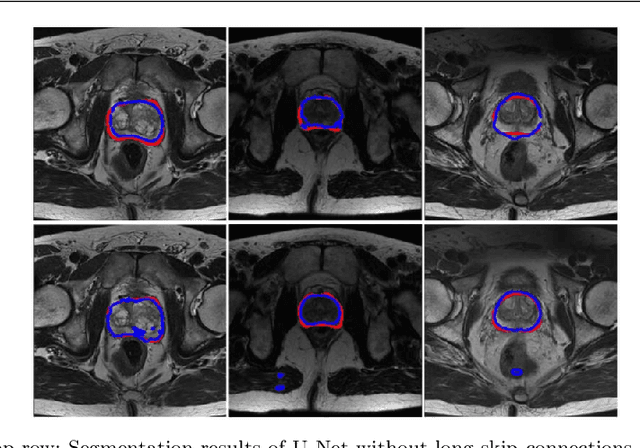

Abstract:Automated medical image segmentation plays an important role in many clinical applications, which however is a very challenging task, due to complex background texture, lack of clear boundary and significant shape and texture variation between images. Many researchers proposed an encoder-decoder architecture with skip connections to combine low-level feature maps from the encoder path with high-level feature maps from the decoder path for automatically segmenting medical images. The skip connections have been shown to be effective in recovering fine-grained details of the target objects and may facilitate the gradient back-propagation. However, not all the feature maps transmitted by those connections contribute positively to the network performance. In this paper, to adaptively select useful information to pass through those skip connections, we propose a novel 3D network with self-supervised function, named selective information passing network (SIP-Net). We evaluate our proposed model on the MICCAI Prostate MR Image Segmentation 2012 Grant Challenge dataset, TCIA Pancreas CT-82 and MICCAI 2017 Liver Tumor Segmentation (LiTS) Challenge dataset. The experimental results across these data sets show that our model achieved improved segmentation results and outperformed other state-of-the-art methods. The source code of this work is available at https://github.com/ahukui/SIPNet.